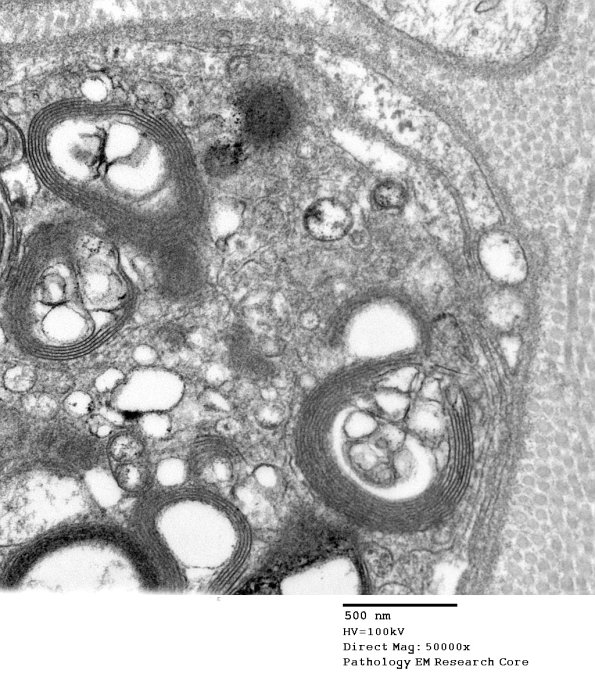

In this case there is demyelination of otherwise normal appearing myelin with axonal preservation. (electron micrograph)